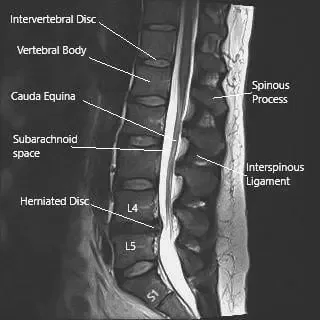

MRI image of the lumbosacral spine in sagittal section showing herniated intervertebral disc at L4-L5 level.

The sciatic nerve’s large size and long course make it particularly vulnerable to compression or injury. The most common cause of irritation is a herniated disc at the L4–L5 or L5–S1 levels, which can compress one or more of the contributing nerve roots. Other causes include spinal stenosis, degenerative disc disease, piriformis syndrome, and direct trauma.

MRI is the most effective imaging tool for assessing sciatic nerve pathology. It can detect disc herniations, spinal canal narrowing, and nerve root compression at the lumbosacral level. CT scans and electromyography (EMG) may also be used to identify bone-related causes or assess nerve function.

An MRI of the lumbosacral spine often reveals the source of compression — most commonly a herniated disc at the L4–L5 level pressing on one of the contributing nerve roots.